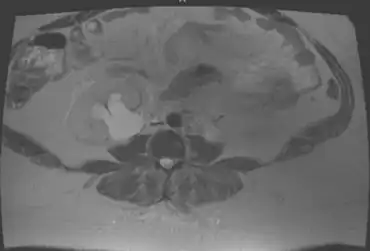

Individual with pelvic malakoplakia showing hydronephrosis

As malakoplakia is a condition associated with chronic cystitis, it usually presents itself as a cystitis condition. The following investigations may help in making the diagnosis of malakoplakia: